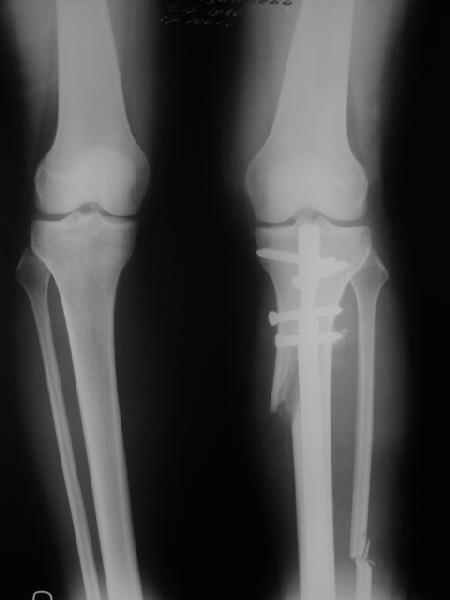

AC> Обратилась дама 25 лет. Вынуждена ходить в брюках из-за genu varum,

AC> что побудило обратиться за коррекцией.

Судя по снимку у девушки имеется внутренняя установка надколенников...

Как у нее с торсионным статусом? Бедро? Голень? КТ? Торсиометры? А то, куда будут

смотреть надколенники после вашей коррекции - тоже существенный

косметический момент. Или не так?

. On the right leg you can see some of the tools (from the tool bar above) applied to demonstrate a mild mech-axis varus of about 5 degrees.

On the left the bone landmarks used in the anlaysis are shown.

The data for the analysis are in the XLs sheet below, exported from the program automatically.

I have given a label of the abreviations and some normative values.

In essence she has a mild mech-axis varus of 7 degrees with some contribution from the femur (2) degrees and more from the tibia (6 degrees), none from the joint.

The analysis took about 6 mins.